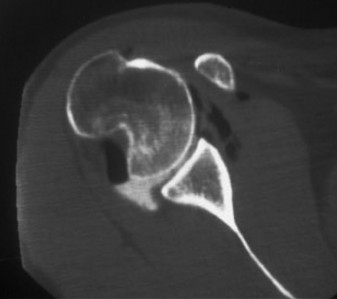

A 17-year-old, football player with a history of multiple, left shoulder dislocations and an attempted arthro…